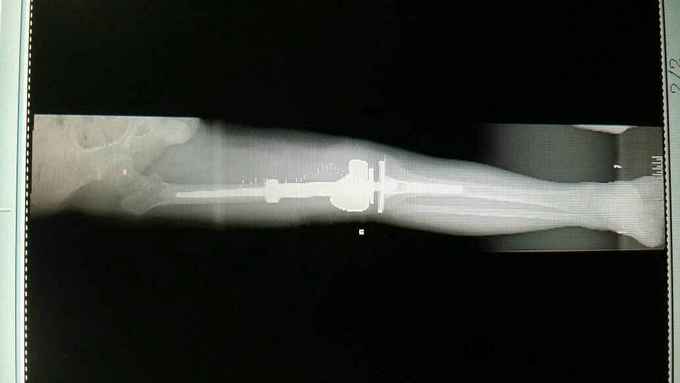

完善术前各项检查,检验,穿刺活检回示:考虑骨肉瘤,参加省病理会诊及北京积水潭会诊回示:符合骨肉瘤,进行术前新辅助化疗,期间定制肿瘤假体,化疗2个周期后,患者复查磁共振,肿块明显缩小,行右股骨远端骨肉瘤肿瘤膝关节置换术。

随访:患者术后化疗4个周期,现患肢功能锻炼良好。 讨论:肿瘤膝关节置换,要求首先明确病例诊断,术前新辅助化疗,术中广泛切除病变组织,包括穿刺点周围组织,术后辅助化疗。